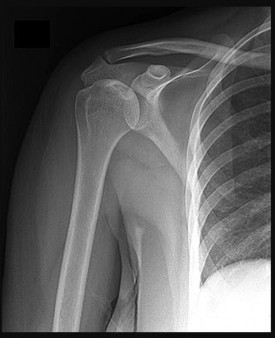

Prepare for the Arab Orthopaedic Board exam with high-yield MCQs, clinical cases, and comprehensive review materials.